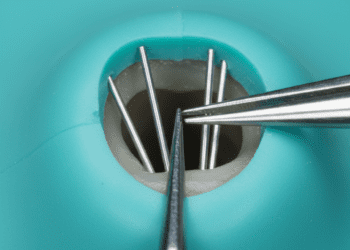

O diagnóstico é realizado por meio da anamnese, exame clínico e testes sensoriais. O dentista deverá analisar os sintomas descritos pelo paciente e avaliar a vitalidade da polpa com métodos que incluem:

- Teste de sensibilidade térmica: Aplicação de frio para verificar a resposta da polpa;

- Teste elétrico de vitalidade: Utilizado para medir a resposta elétrica da polpa;